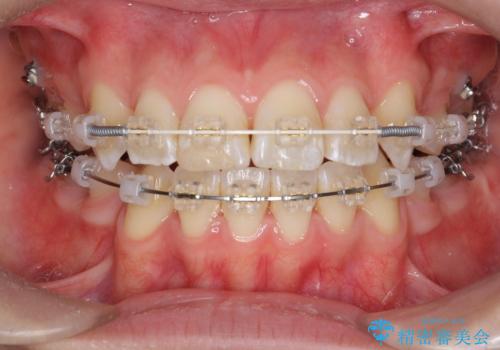

突き出た前歯を治したい 小臼歯抜歯+マルチブラケット矯正

- 矯正装置

- ワイヤー矯正

前歯の角度を改善するために小臼歯4本の抜歯を行いワイヤー マルチブラケットを用いて、しっかりと前歯の角度を改善する治療計画としました。